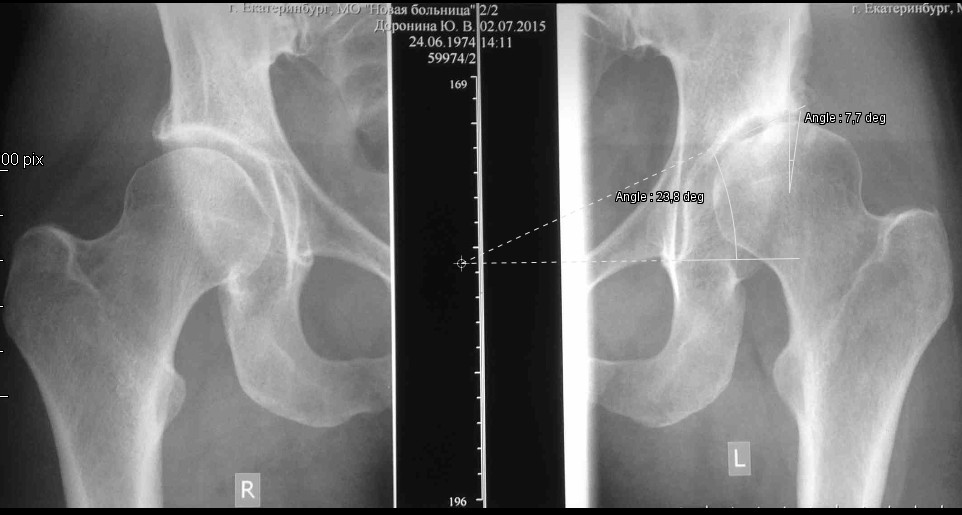

[Ortho] FAI